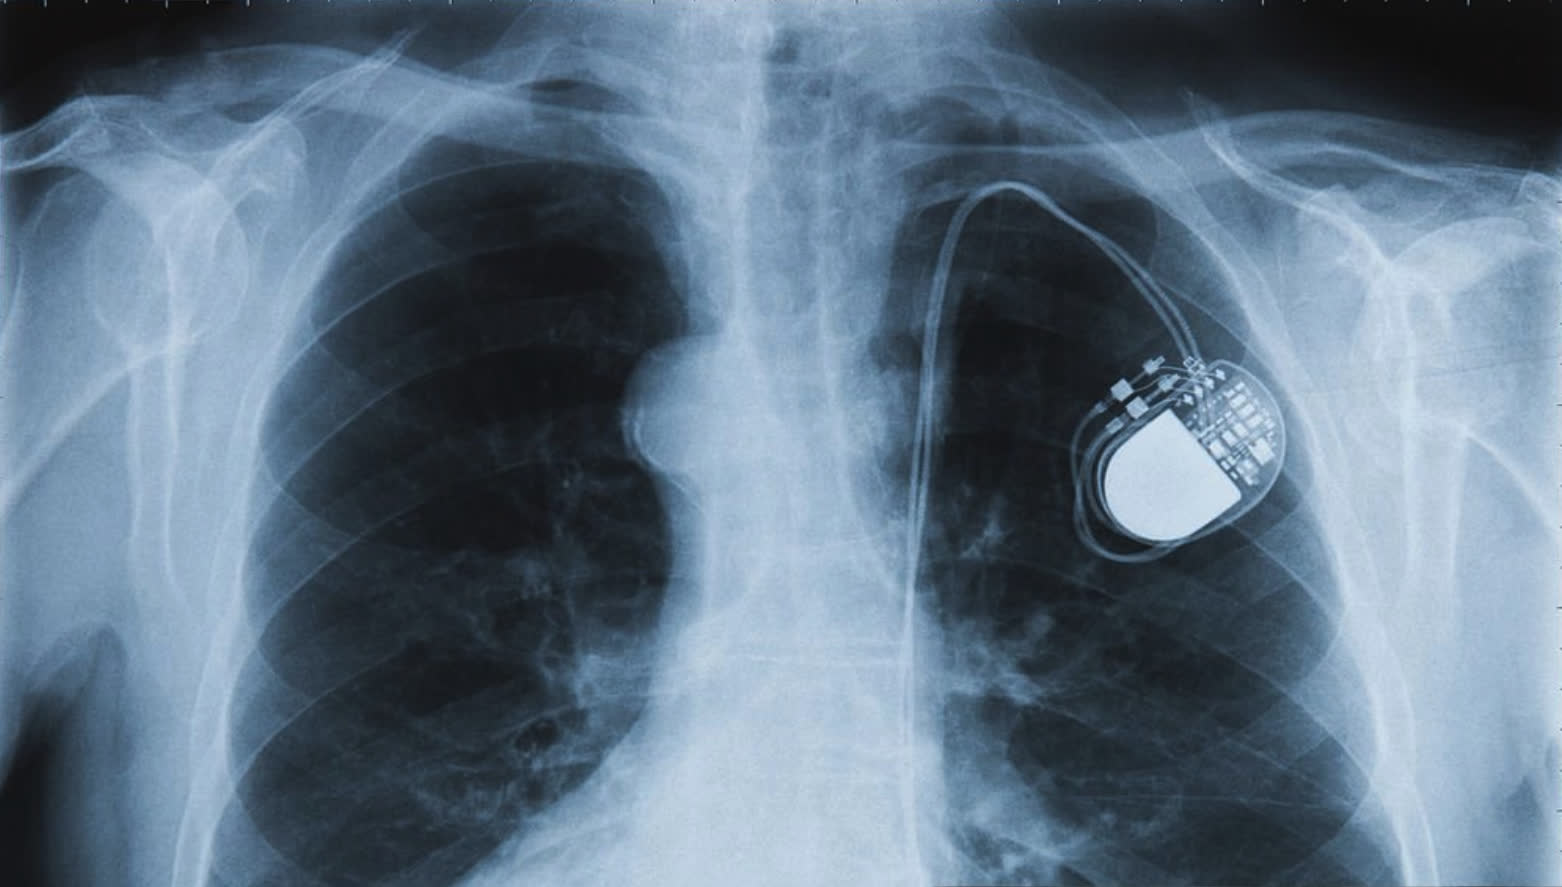

心臟起搏器是由脈衝產生器、用來連接脈衝產生器和心臟的電極線所組成。心跳過慢通常是由病態竇房結綜合症或心臟房室傳導阻塞引致,患者通常為長者,心跳會時快時慢,心跳過快的情況會增加中風風險,可由藥物加以幫助,而心跳過慢時,則需要安裝心臟起搏器,目的是刺激心臟令心律回復正常,控制心跳不會慢過每分鐘60次。心律過慢可引致頭暈、暈厥、心臟衰竭,或在少數情況下引致心臟猝死。心臟起搏器作長期醫治心律過慢之用,若心跳持續過慢,甚至出現3秒以上的停頓情況,一般都需要植入心臟起搏器來調校正常心律。

甄秉言表示:「有時心臟慢了或心臟老化,也就是心臟『電線』開始壞,心跳開始慢到人會暈,起搏器可以保持心跳,不要讓心跳下降,維持心跳底線。」而心臟起搏器通常都會設一個安全底線,因為是預防性問題,不需要設得很高,不讓心跳下降,「好像緊急燈停電了就開,不需要它的時候就不用,心跳一跌,它即刻就會幫你增加心跳。」